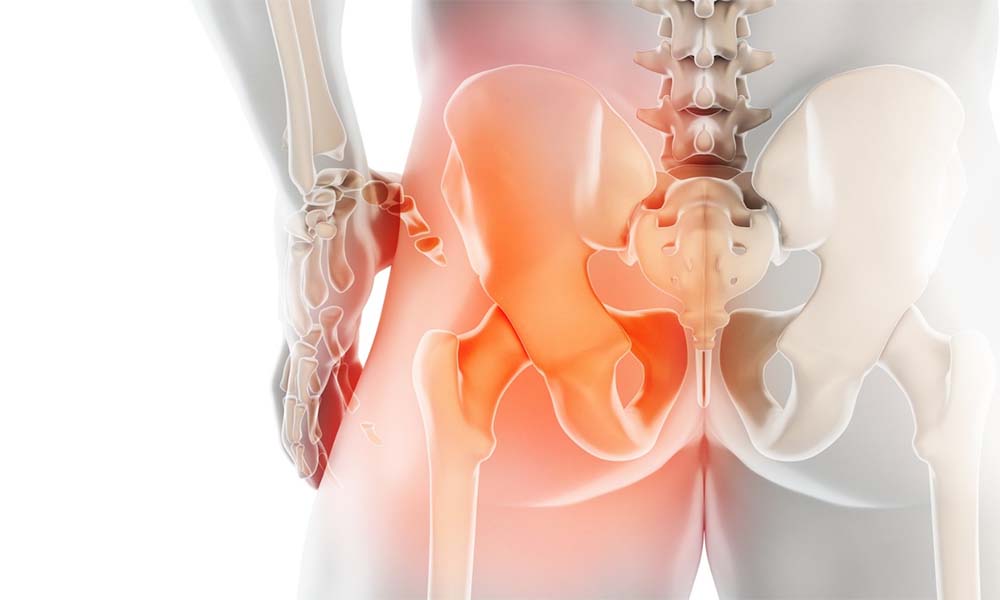

Total kalça protezi ameliyatı, ileri derecede kalça eklemi hasarı için etkili tedavidir. Osteoartrit, romatoid artrit, kırık veya doğuştan eklem bozuklukları gibi durumlar içni uygulanır. Total kalça protezi ameliyatı sonrası, yaşam kalitesini artırmada en az ameliyat kadar önemlidir.

Total kalça protezi ameliyatı, hastaların hareket kabiliyetini artıran ve ağrıyı azaltan cerrahi işlemdir. Ancak ameliyatın başarısı, büyük ölçüde iyileşme sürecine bağlıdır. Ameliyat sonrası dikkat edilmesi gerekenler, sağlıklı bir iyileşme için kritik öneme sahiptir.

Total kalça protezi ameliyatı, hastaların yaşam kalitesini artırmada etkili bir tedavi yöntemidir. Ancak ameliyat sonrası süreç büyük önem taşır. Protezin sağlıklı bir şekilde işlevini sürdürebilmesi ve komplikasyonların önlenmesi bu döneme bağlıdır.